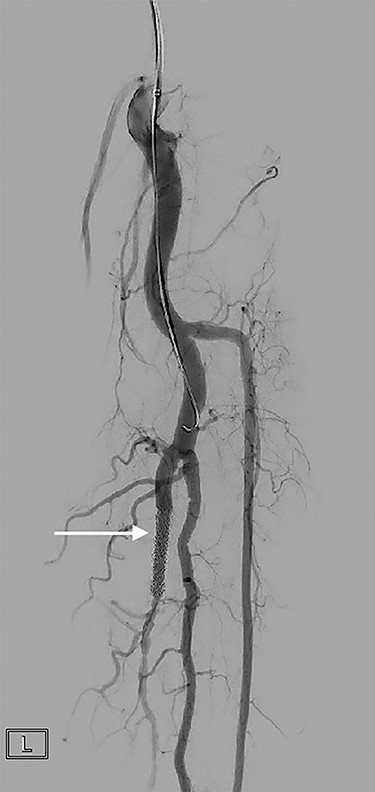

Formal angiogram was undertaken and posterior tibial AVF was confirmed (Fig. 1). Two Advanta V12 polytetrafluoroethylene covered balloon-expandable stents were placed in the posterior tibial artery (Merrimack, NH, USA): 5 × 22 mm distally and 6 × 22 mm proximally, resulting in successful exclusion of the fistula (Fig. 2).

A covered stent (arrow) deployed in the posterior tibial artery occludes flow through the fistula. Contrast flows into the arterial tree without shunting into the venous system.